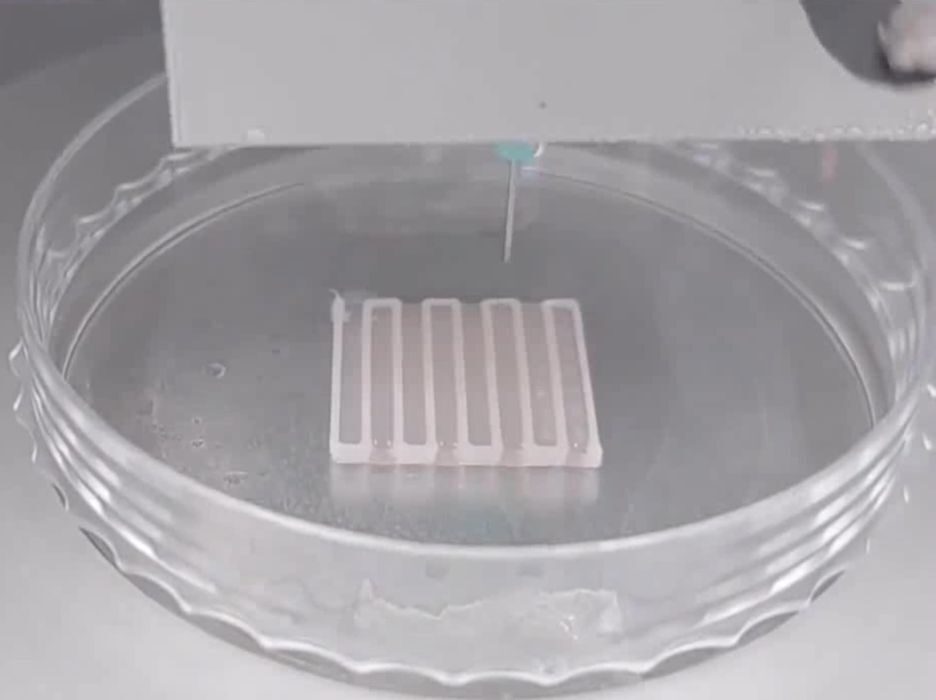

Researchers 3D Print Functional Blood Vessels Using Custom Bioink

Researchers have developed a method of 3D printing blood vessels, and that’s quite important.